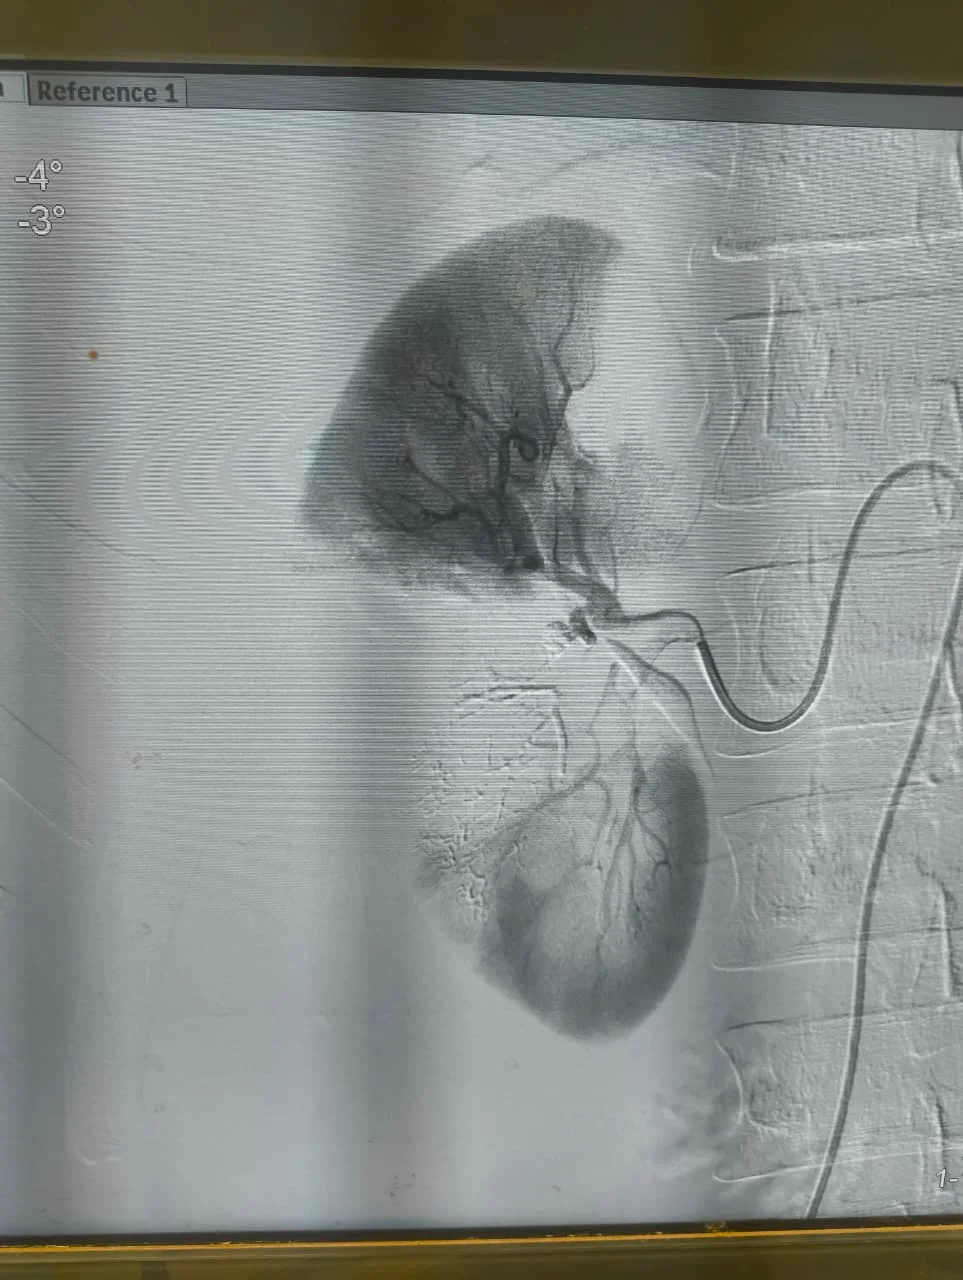

استمرارًا لمسيرة النجاح التى يحققها مستشفى كفر الشيخ الجامعى فى تقديم خدمات طبية متقدمة، نجح الفريق الطبى بوحدة الأشعة التداخلية تحت إشراف الدكتور محمود غلابمدير وحدة الأشعة التداخلية و استشارى الأشعة التداخلية، و زميل الأشعة التداخلية بجامعة هيروشيما، و مدرس الأشعة التداخلية بجامعة كفر الشيخ – فى إنقاذ حياة شاب تعرّض لحادث أدى إلى قطع جزئى فى الشريان الكلوى الأيمن مصحوبًا بتجمع دموى، و ذلك دون اللجوء إلى استئصال الكُلى.

تمكّن فريق الأشعة التداخلية بجامعة كفر الشيخ بقيادة د. محمود غلاب من إجراء تدخل طارئ ناجح تم خلاله سدّ التمدد الشريانى مع الحفاظ الكامل على التغذية الدموية لباقى أنسجة الكُلى، و هو ما يُعد من أبرز و أهم مميزات الأشعة التداخلية التى تهدف إلى إنقاذ العضو المصاب دون جراحة مفتوحة، و بأعلى درجات الدقة مع تقليل المضاعفات و فترة التعافى.

تم إجراء هذا التدخل فجر يوم الاثنين بعد ساعات قليلة من الإبلاغ عن حالة المريض المحجوز بالمستشفى العام، حيث جرى تنسيق عاجل مع إدارة مستشفى كفر الشيخ الجامعى لتوفير جميع المستلزمات الطبية اللازمة، و تم نقل المريض على الفور إلى المستشفى الجامعى لإجراء التدخل و إنقاذ حالته فى توقيت حرج.